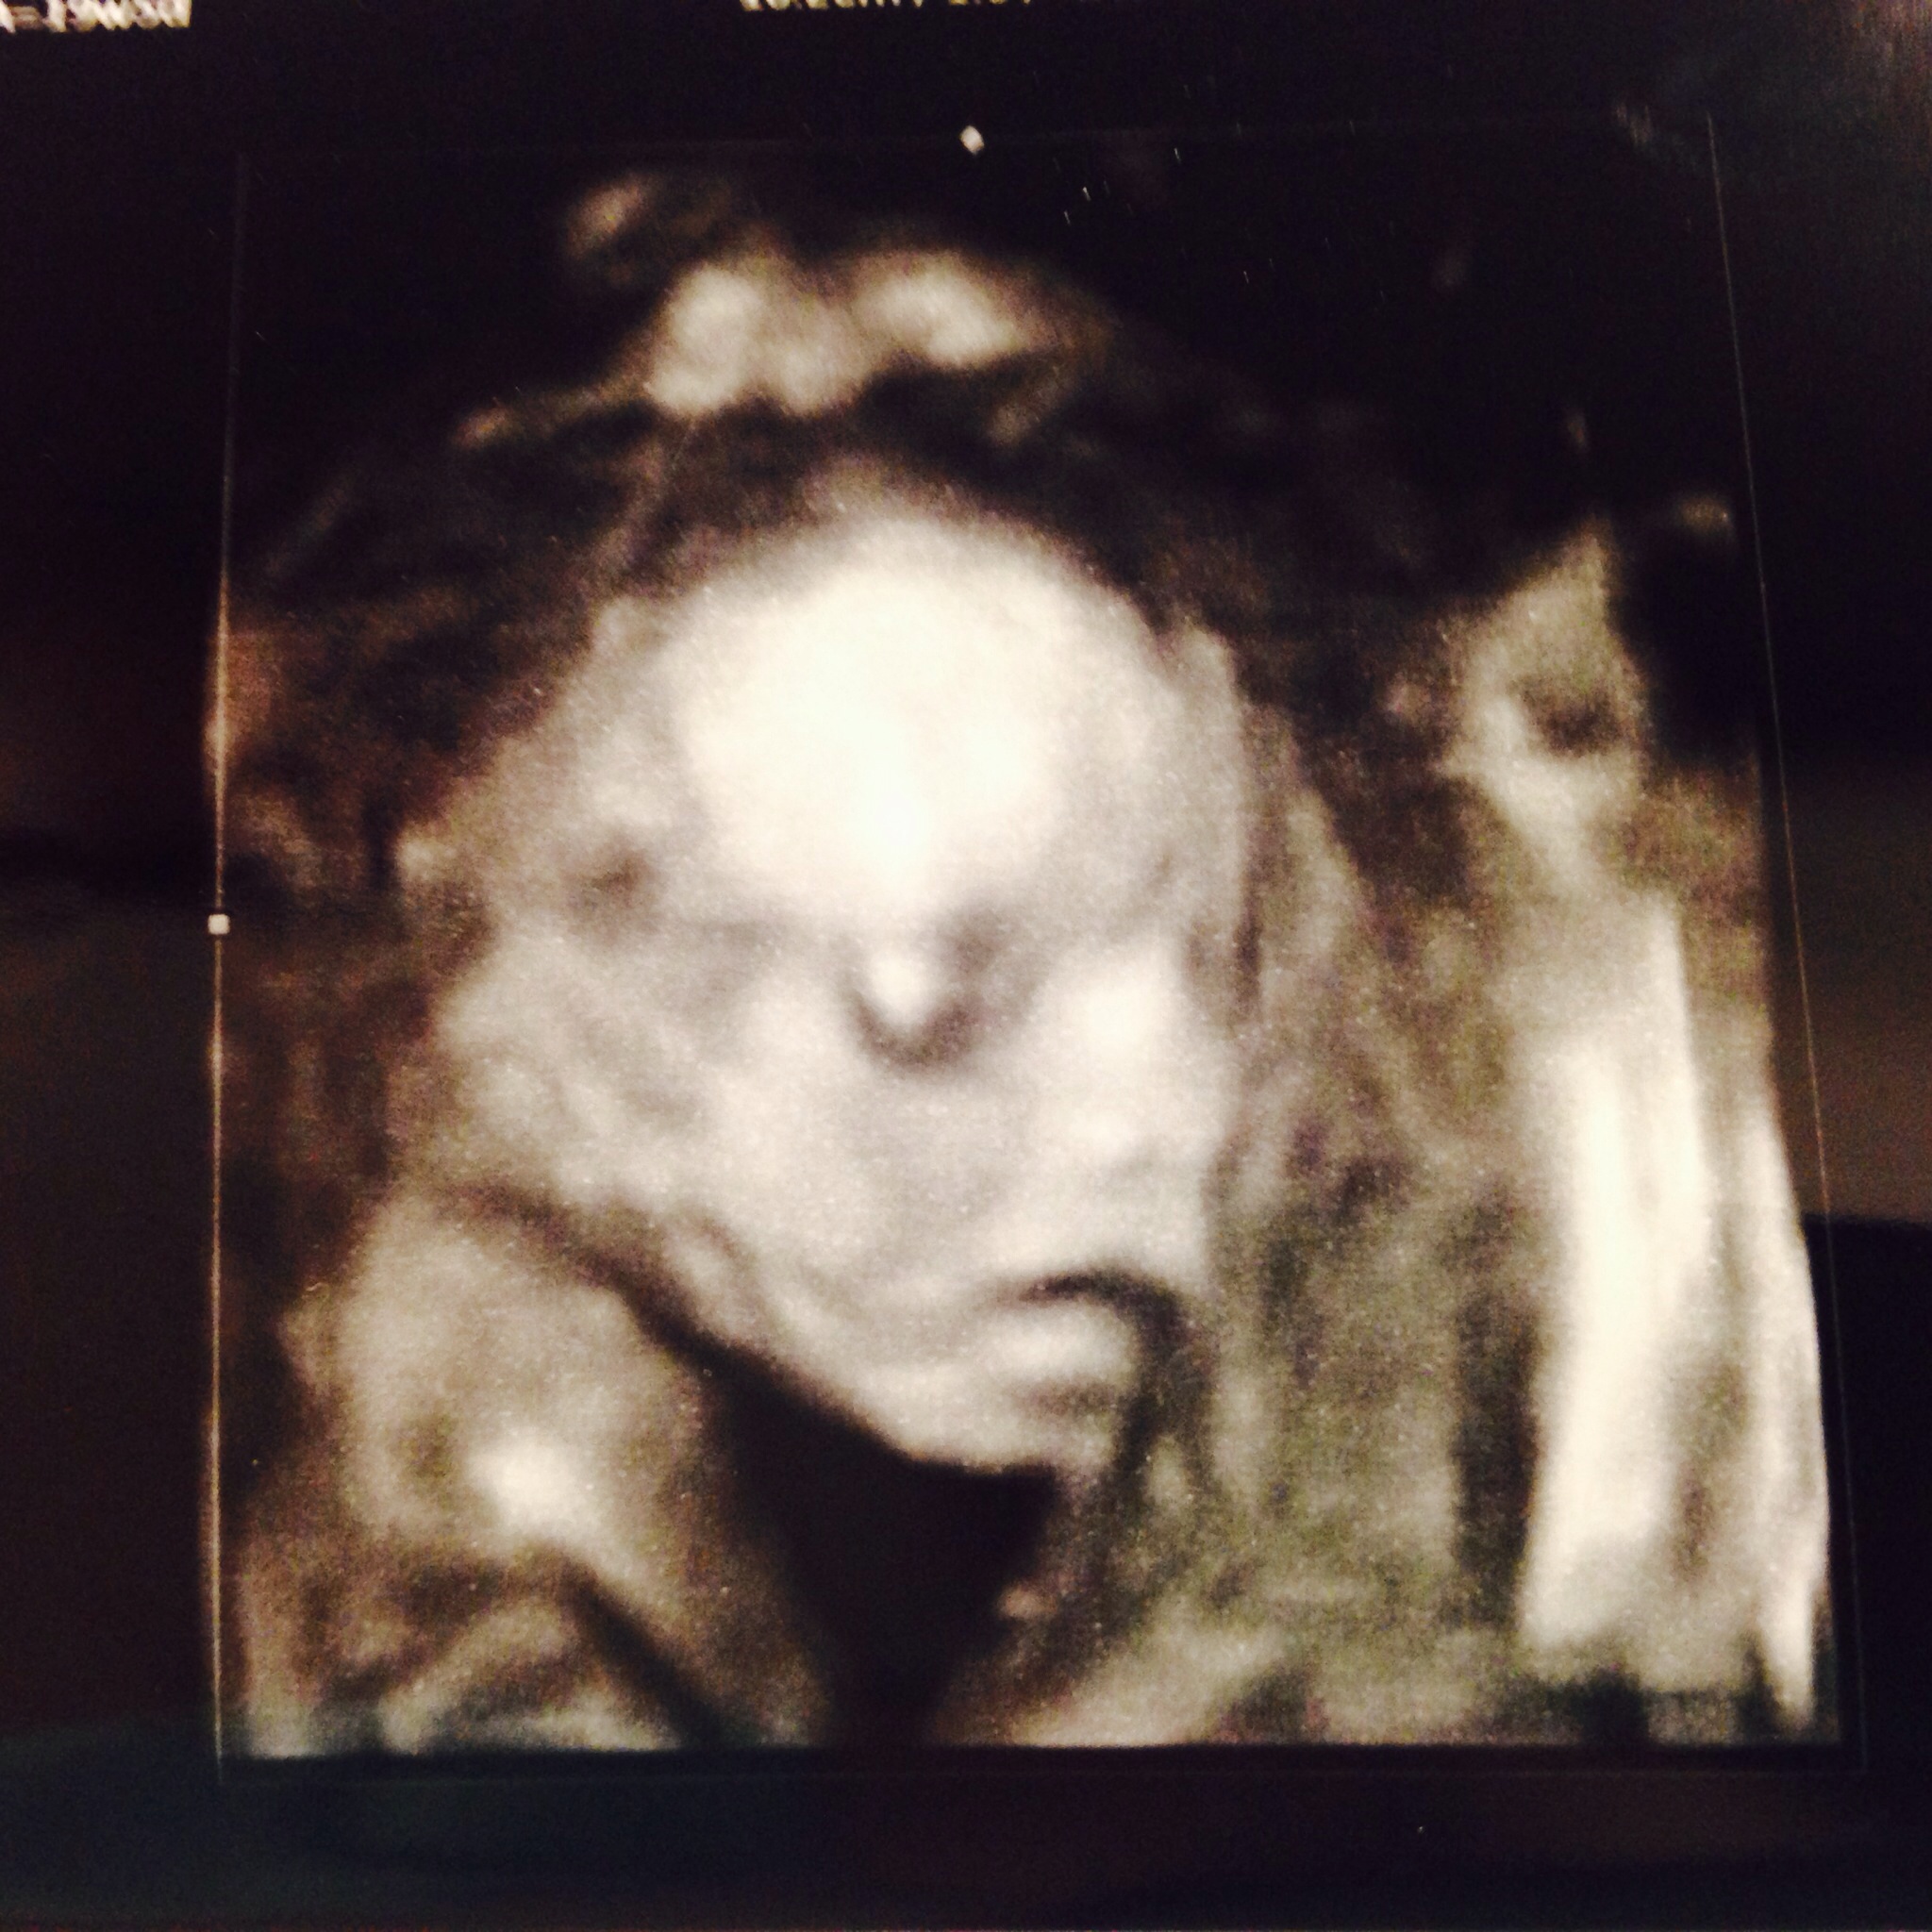

Had my a/s yesterday. I drank a bunch of fruit juice before hand and baby was moving all over. Held strong with team green. Baby was upside down for most of the scan and it took about an hour so it was great seeing him/her for so long: Everything looked great but the tech couldn't get a few measurements so we are going back again in a month!